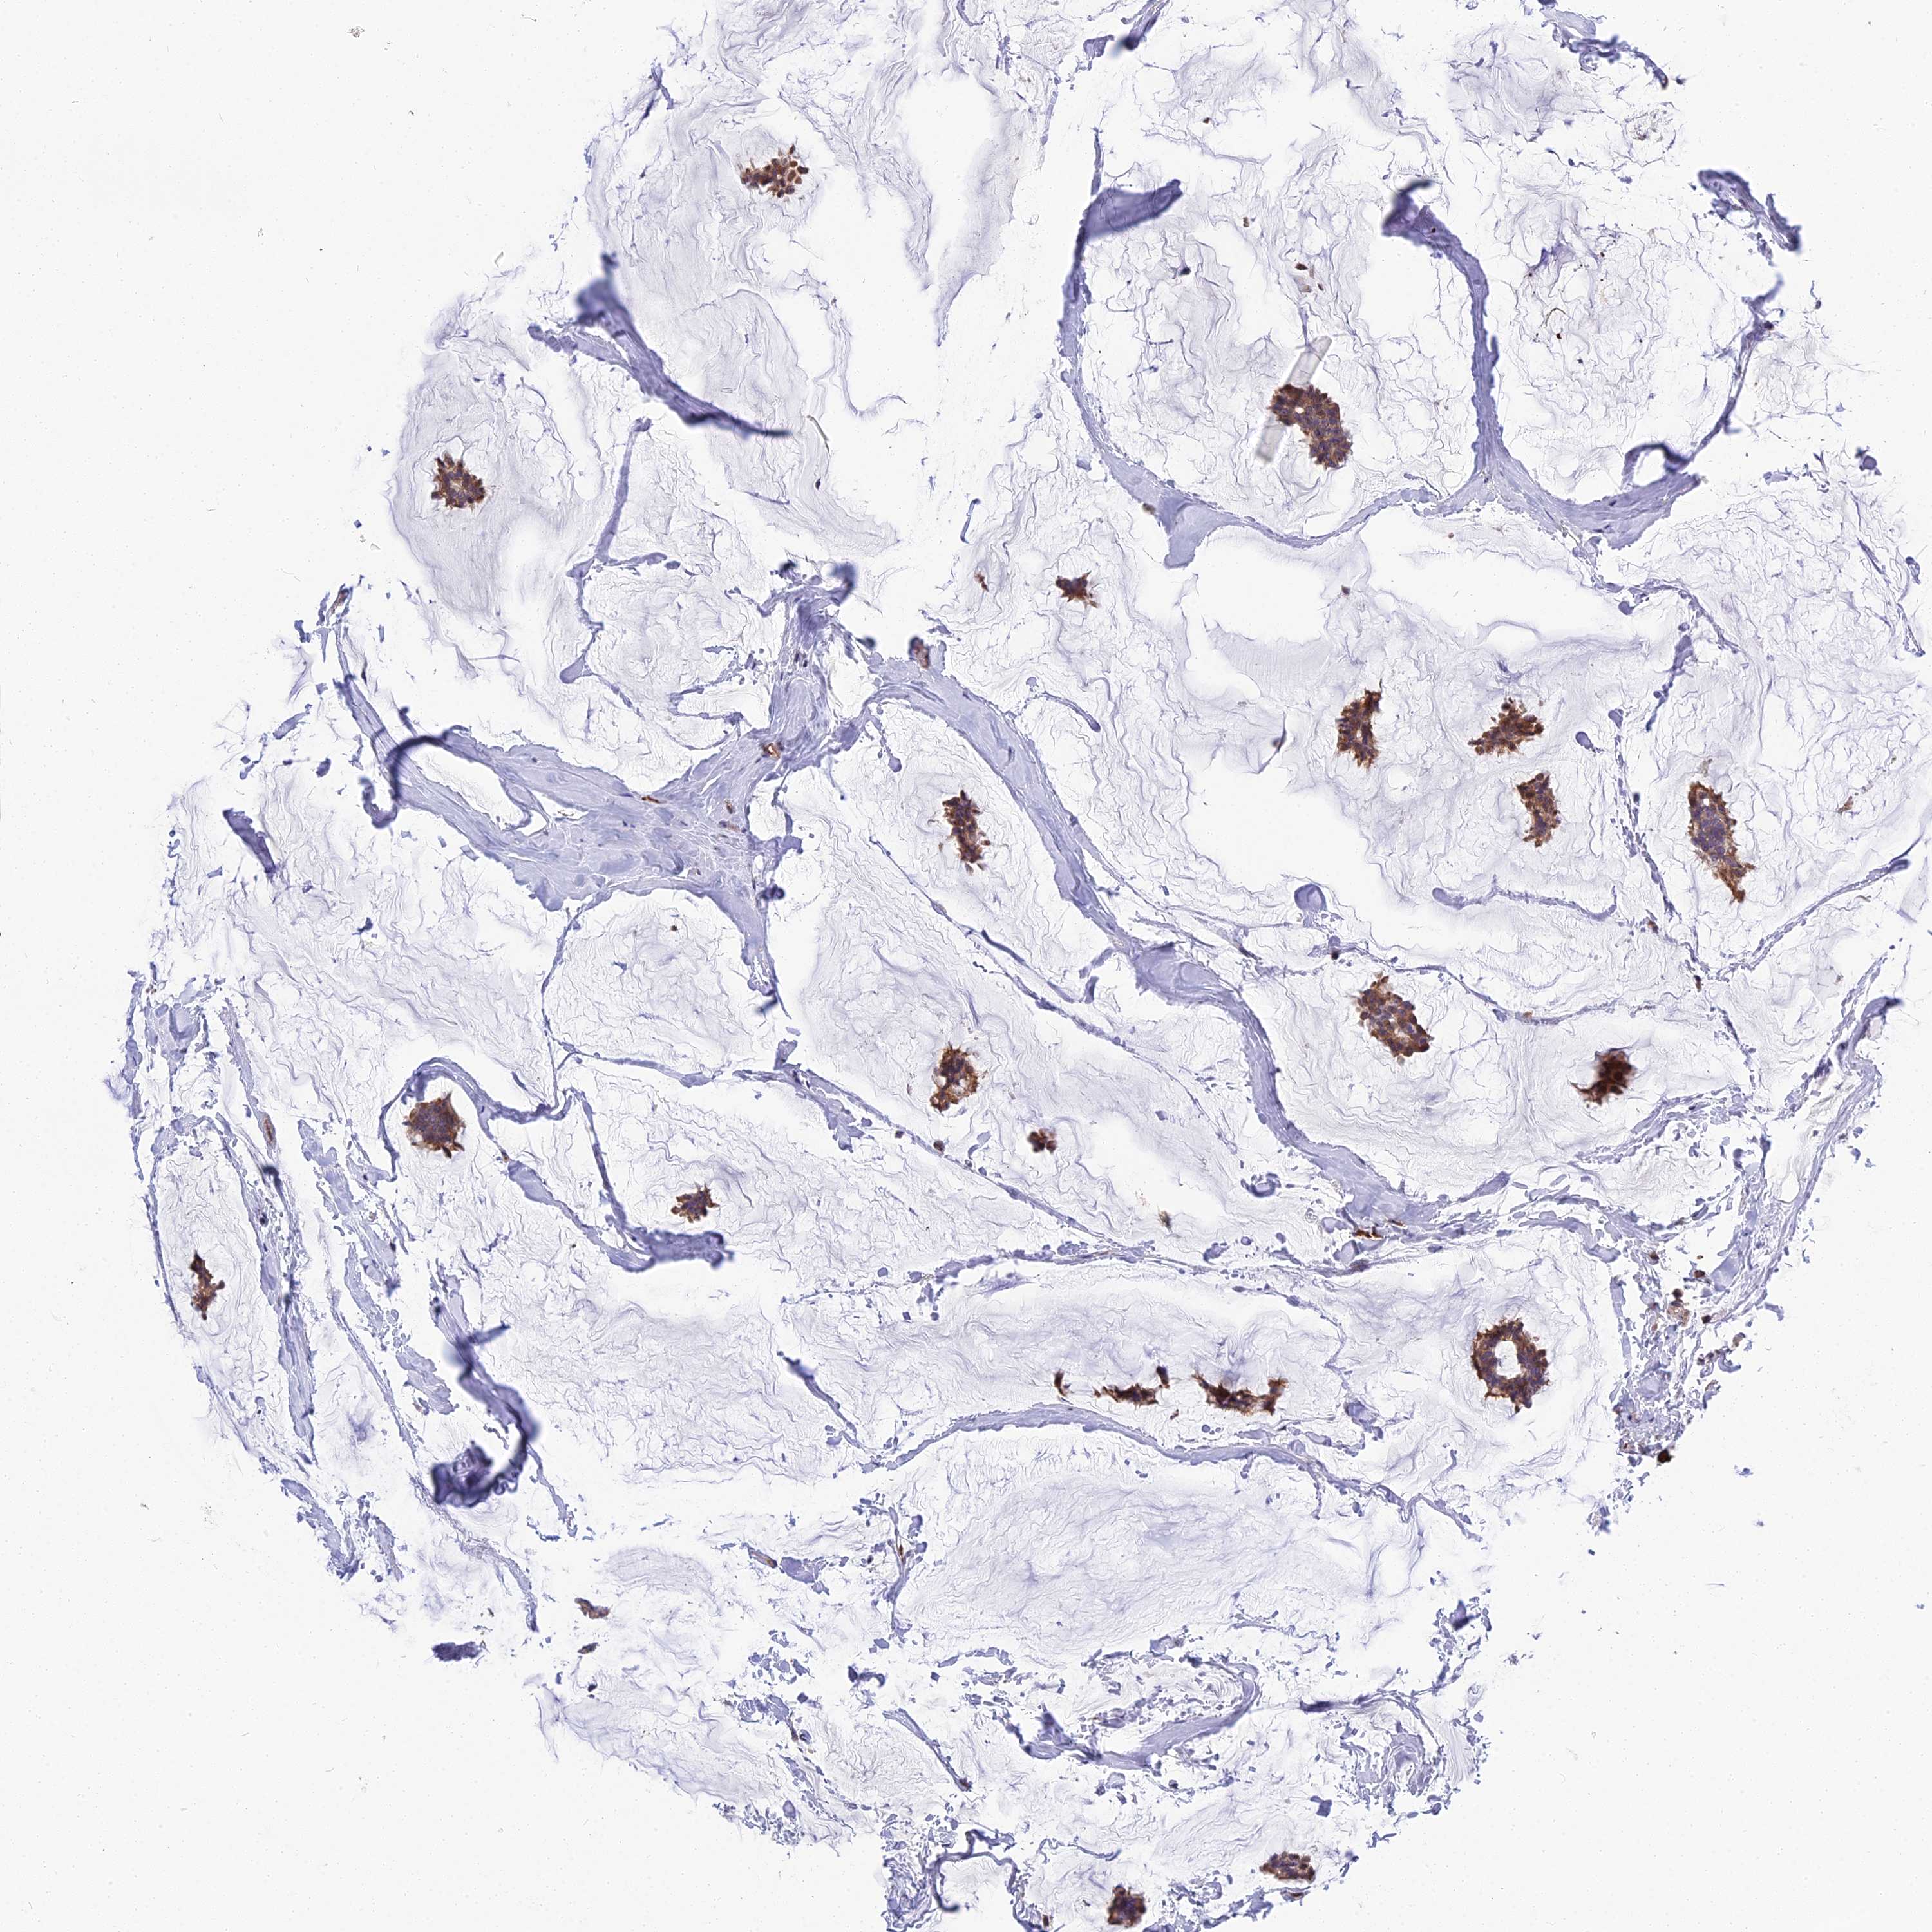

CANCER BREAST CANCER Show tissue menu

BRCA TCGA BRCA VALIDATION PROTEIN EXPRESSION